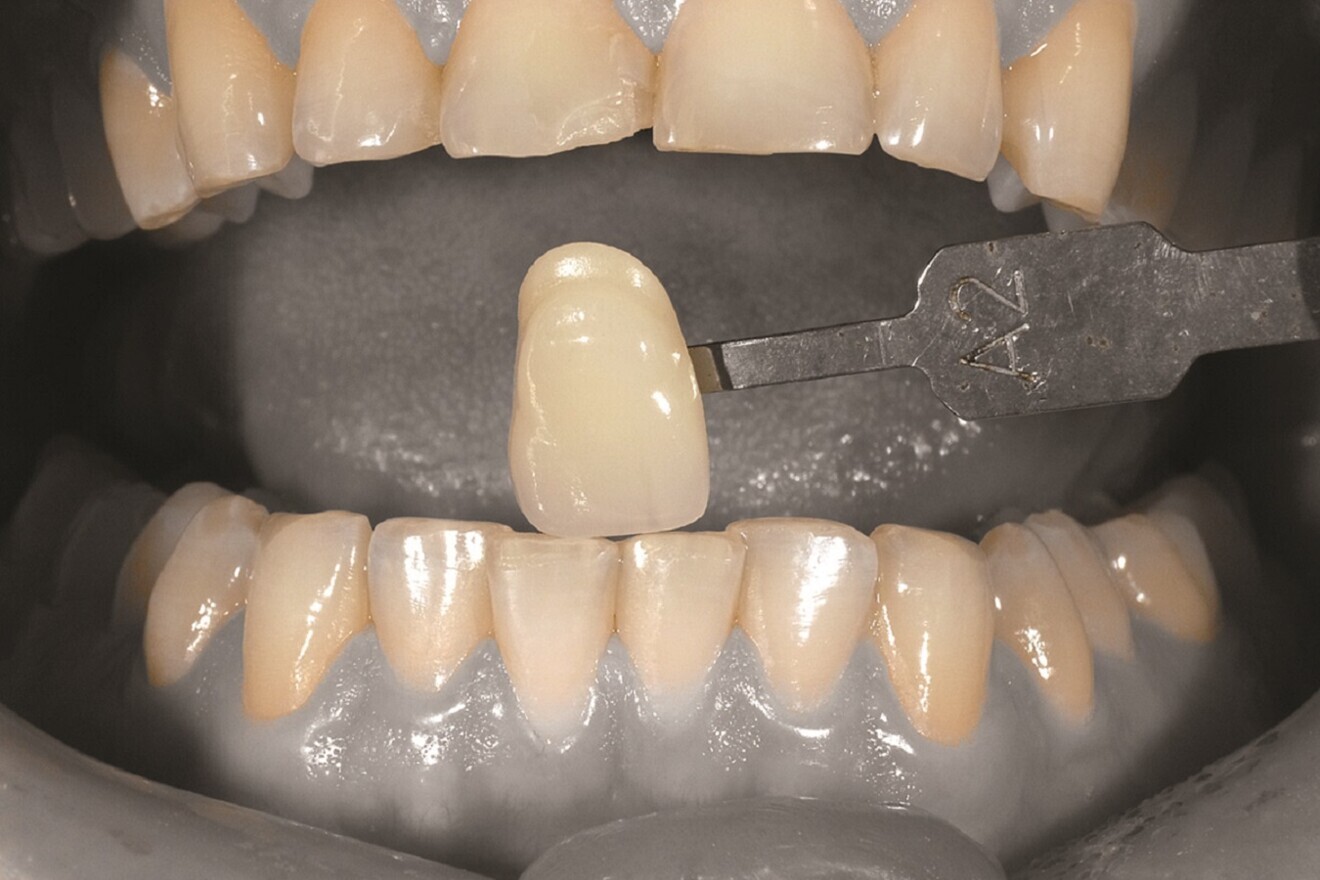

First operative procedure: Direct composite veneer of tooth #41

Fig. 4: Shade taking prior to restoration.